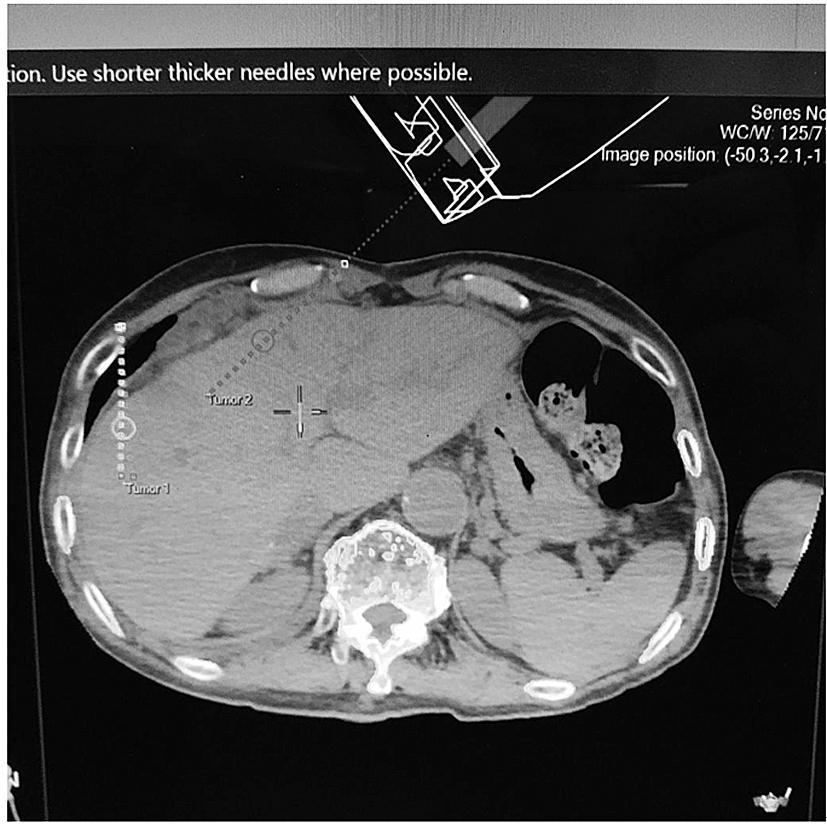

机器人可以设定高难度的进针路线。图中消融近肝包膜及膈顶病灶设计斜行进针路线,避开肺脏和肝内脉管。

制订消融进针计划,设定消融参数,使消融区覆盖瘤体。

3D显示消融针进针路线及消融范围

机器人助力介入科医生完成全麻下CT引导肝肿瘤微创消融手术